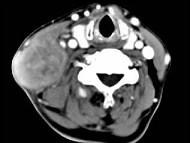

问题 65岁男性,吸烟史30余年,近半年来颈部出现疼痛性肿块,CT扫描如图所示,请选择最可能诊断 ( )

选项 A、淋巴结转移癌 B、软组织脓肿 C、血管瘤 D、神经鞘瘤 E、淋巴结核

答案 A